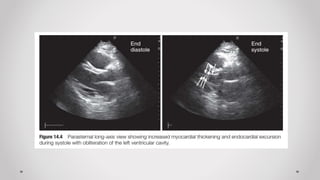

a) Mặt cắt dọc cạnh ức (Parasternal long axis plane)

2. Đánh giá chức năng thất Trái

Trường hợp không có máy siêu âm tim chuyên biệt  có thể đánh giá bằng “mắt” các

tiêu chí sau của thất Trái:

a) Kích thước: buồng tim (bình thường/giãn), cơ tim (bình thường, dày, mỏng)

b) Hình dạng: hạt đậu, trái chuối

c) Chức năng co bóp: bình thường, tăng, giảm

d) Vận động vùng: bình thường, nghịch thường, giảm động, vô động